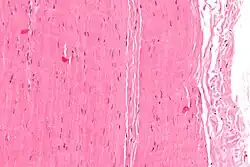

Tkanka miękka – tkanka, która łączy, wspiera, lub otacza narządy organizmu i nie jest tkanką chrzęstną ani tkanką kostną. Do tkanek miękkich zalicza się: tkankę łączną, tkankę nabłonkową, tkankę mięśniową oraz tkankę nerwową[1]. Komórki budujące tkankę miękką są bardzo nawodnione, a charakterystycznym substancjami występującymi wewnątrz macierzy pozakomórkowej tkanki miękkiej są kolagen i elastyna. Komórkami odpowiedzialnymi za tworzenie tkanki miękkiej są fibroblasty[2].